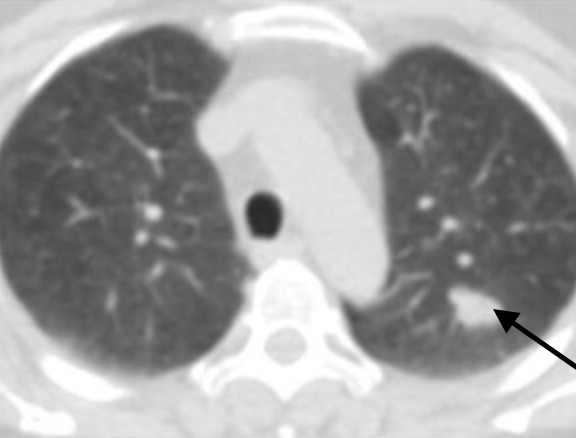

Exemple: la tumeur se situe dans le lobe supérieur gauche : au vu de la taille de la lésion, la chirurgie pourra se faire sous vidéothorascopie et consistera en une lobectomie supérieure gauche avec curage ganglionnaire

Exemple: ici, la tumeur est située dans le lobe supérieur droit du poumon. Le traitement consistera donc en une lobectomie supérieure droite avec curage ganglionnaire. Au vu de la taille importante de la tumeur (plus de 6 cm), la chirurgie sera par voie d’abord ouverte classique.